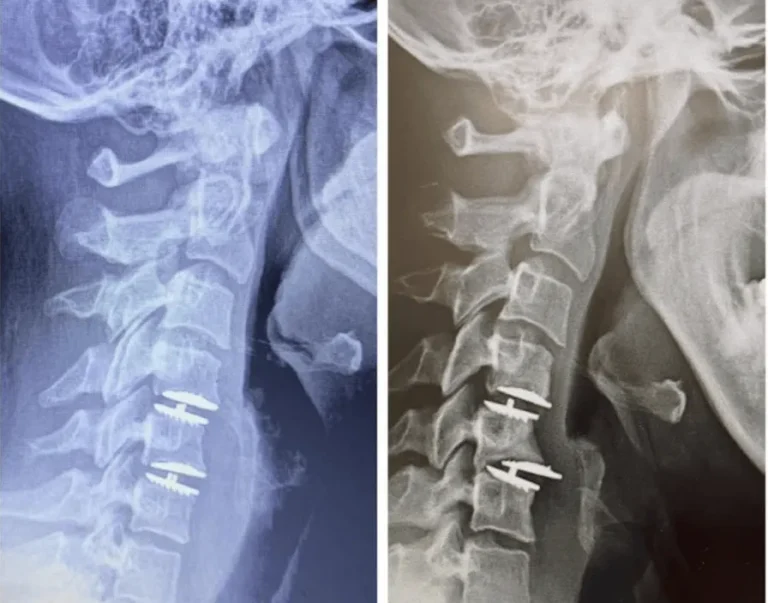

Two X-rays of a neck showing spinal screws in the vertebrae.

X-ray of a neck showing metal screws and plates in the cervical spine.

Side-by-side spinal X-rays showing vertebrae with surgical screws inserted.